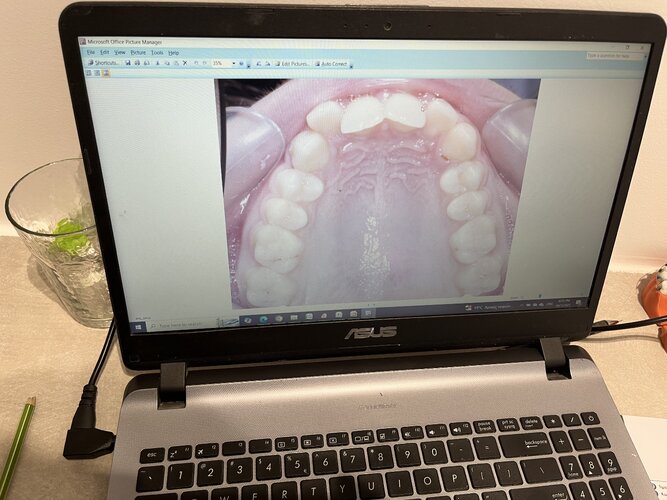

Important to note that my maxilla wasn’t downward grown until braces and headgear I am still 16 and upward thumb pressure is is not really doing anything much (I also had to fix my skeletal issue with my palate because my ortho only did tooth expansion instead of marpe/sarpe (aka breathing issues)